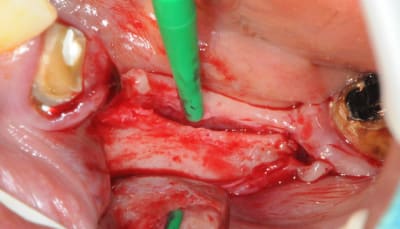

j'ai une photo de chir mais tu ne me feras pas croire que l'on peut mettre des implants là dedans!

je reviens sur ce cas que j'ai un peu délaissé...

il est terminé, j'ai juste oublié de mettre la suite.

-cicatrisation

-mise en place vis de cica petit diamètre

-ensuite on augmente le diamètre en conservant et en gonflant les tissus gingivaux